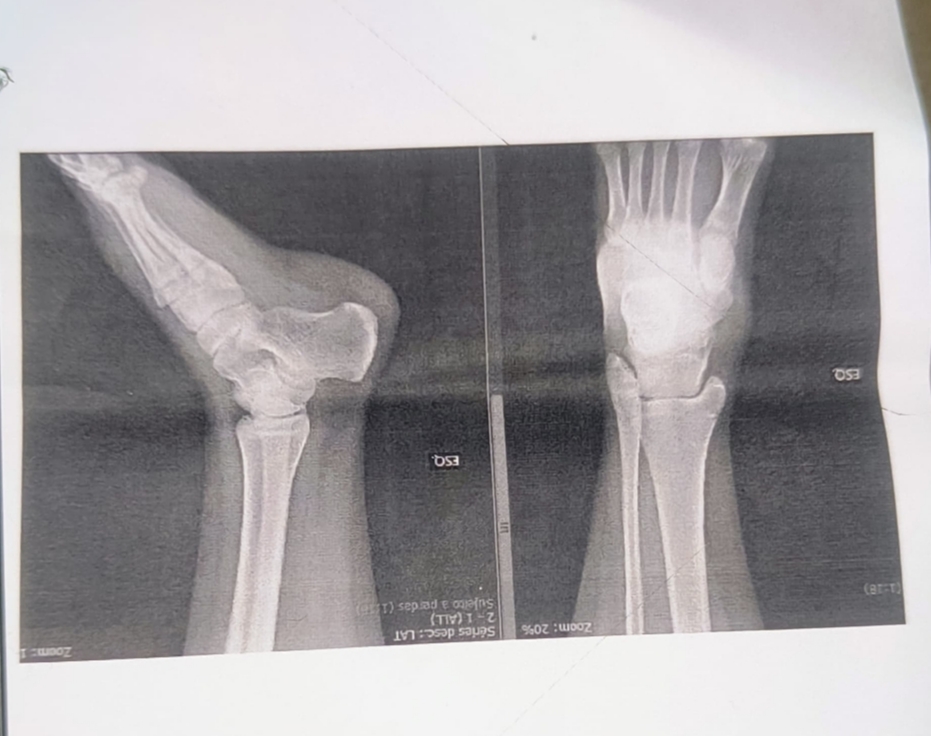

De acordo com a mãe, a filha foi classificada como caso de urgência devido à dor intensa e ao inchaço no pé, que já apresentava coloração roxa. No atendimento médico, porém, o diagnóstico teria sido de luxação, sem fratura. A adolescente realizou raio-X e foi liberada com prescrição de dipirona e orientação para manter o pé elevado por três dias.

Depois de passar a noite com dores, a adolescente foi levada na UPA Vila Almeida, onde a médica a encaminhou ao Cenort. No atendimento com ortopedista, ele reavaliou o exame de raio-X realizado no domingo constatando fratura em dois pontos, com indicação cirúrgica.

Foto: Reprodução